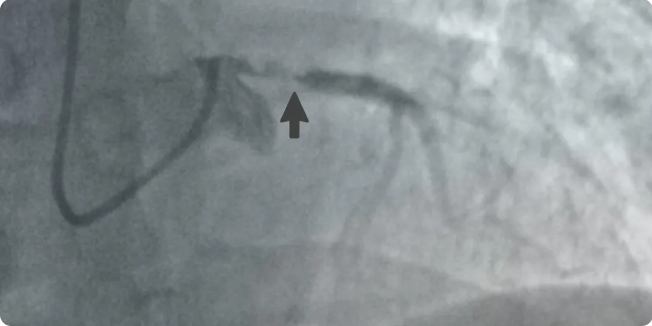

16:06,从确诊到开始手术,仅用时34分钟。冠脉造影揭示了命悬一线的真相:心脏的“总闸门”——左主干末端堵塞90%,其最主要分支前降支完全闭塞。这块为心脏超过三分之二区域供血的核心区域,命悬一线。左主干病变因其极高死亡率,在医学界被称为“寡妇血管”。

手术中,患者血压骤降,循环不稳。“启动IABP(主动脉内球囊反搏)!”主刀医生、心血管内科副主任医师姚常果断下令。这台“心脏辅助泵”迅速运转,为濒临崩溃的心脏提供了最关键的支持。

在生命支持系统的护航下,姚常带领副主任医师闫博宇、主治医师刘兴龙展开精准操作。抽吸、开通、植入……每一步都如履薄冰,争分夺秒。

16:28,决战告捷,堵塞的“生命主干道”被成功打通,血流恢复。此刻,计时器定格在:距患者入院,整整60分钟。